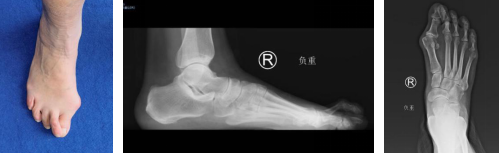

51岁的张大姐,右足踇外翻畸形10年,第一跖趾关节间断性疼痛,越来越严重,听从朋友家人建议后,来到betway在线登陆足踝科就诊。

门诊医生检查,张大姐右足踇外翻畸形,踇囊炎,右足第2趾爪形趾,想要消除疼痛,需要进行矫形治疗。

术前

手术设计